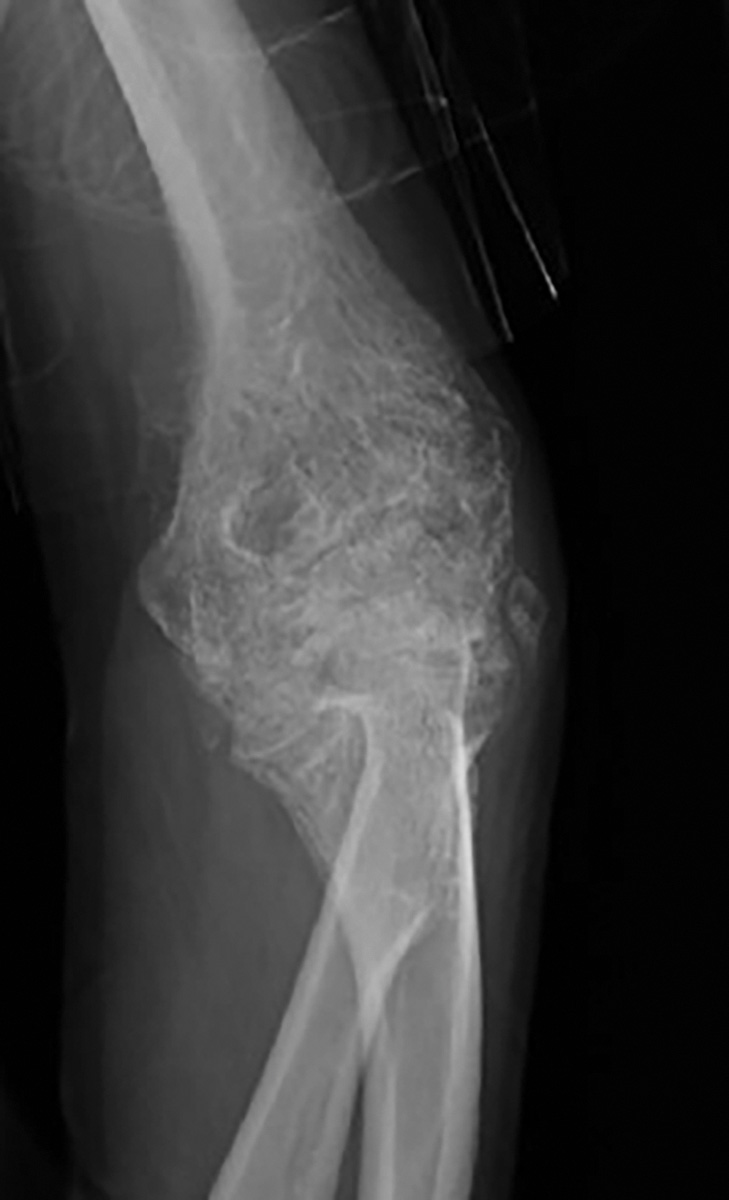

Ectopic or heterotopic bone formation is common to a range of pathologic conditions variably named and described by cause and anatomic location. Whereas heritable conditions of ectopic bone formation such as myositis ossificans progressive were described as early as 1692 by Dr. Patin in pediatric patients, recognition of HO forming after trauma is a relatively recent phenomenon. , One of the earliest descriptions of posttraumatic HO can be found in the work of Drs. DéJerine and Ceillier in 1918 under the name paraosteoarthropathy . At the time it was described as a consequence of neurologic injury, specifically of traumatic paraplegia after spinal cord injury (SCI), and was primarily presented as a condition of the hip and lower extremities. In the ensuing decades, awareness of the disease grew slowly; scattered case reports of periarticular and intramuscular sites after thermal and musculoskeletal injuries were published. In this period, HO of the elbow was first recognized as a consequence of severe burns ( Fig. 20.6 ). In the intervening years as the number of cases has grown, the relationship between orthopedic and neurologic injury and surgery have expanded and the modern paradigm of an inflammation-driven pathologic condition affecting any of the myriad connective tissues investing every anatomic structure in the human body has gained greater support.

Radiograph demonstrating ectopic bone formation around the elbow after thermal injury.